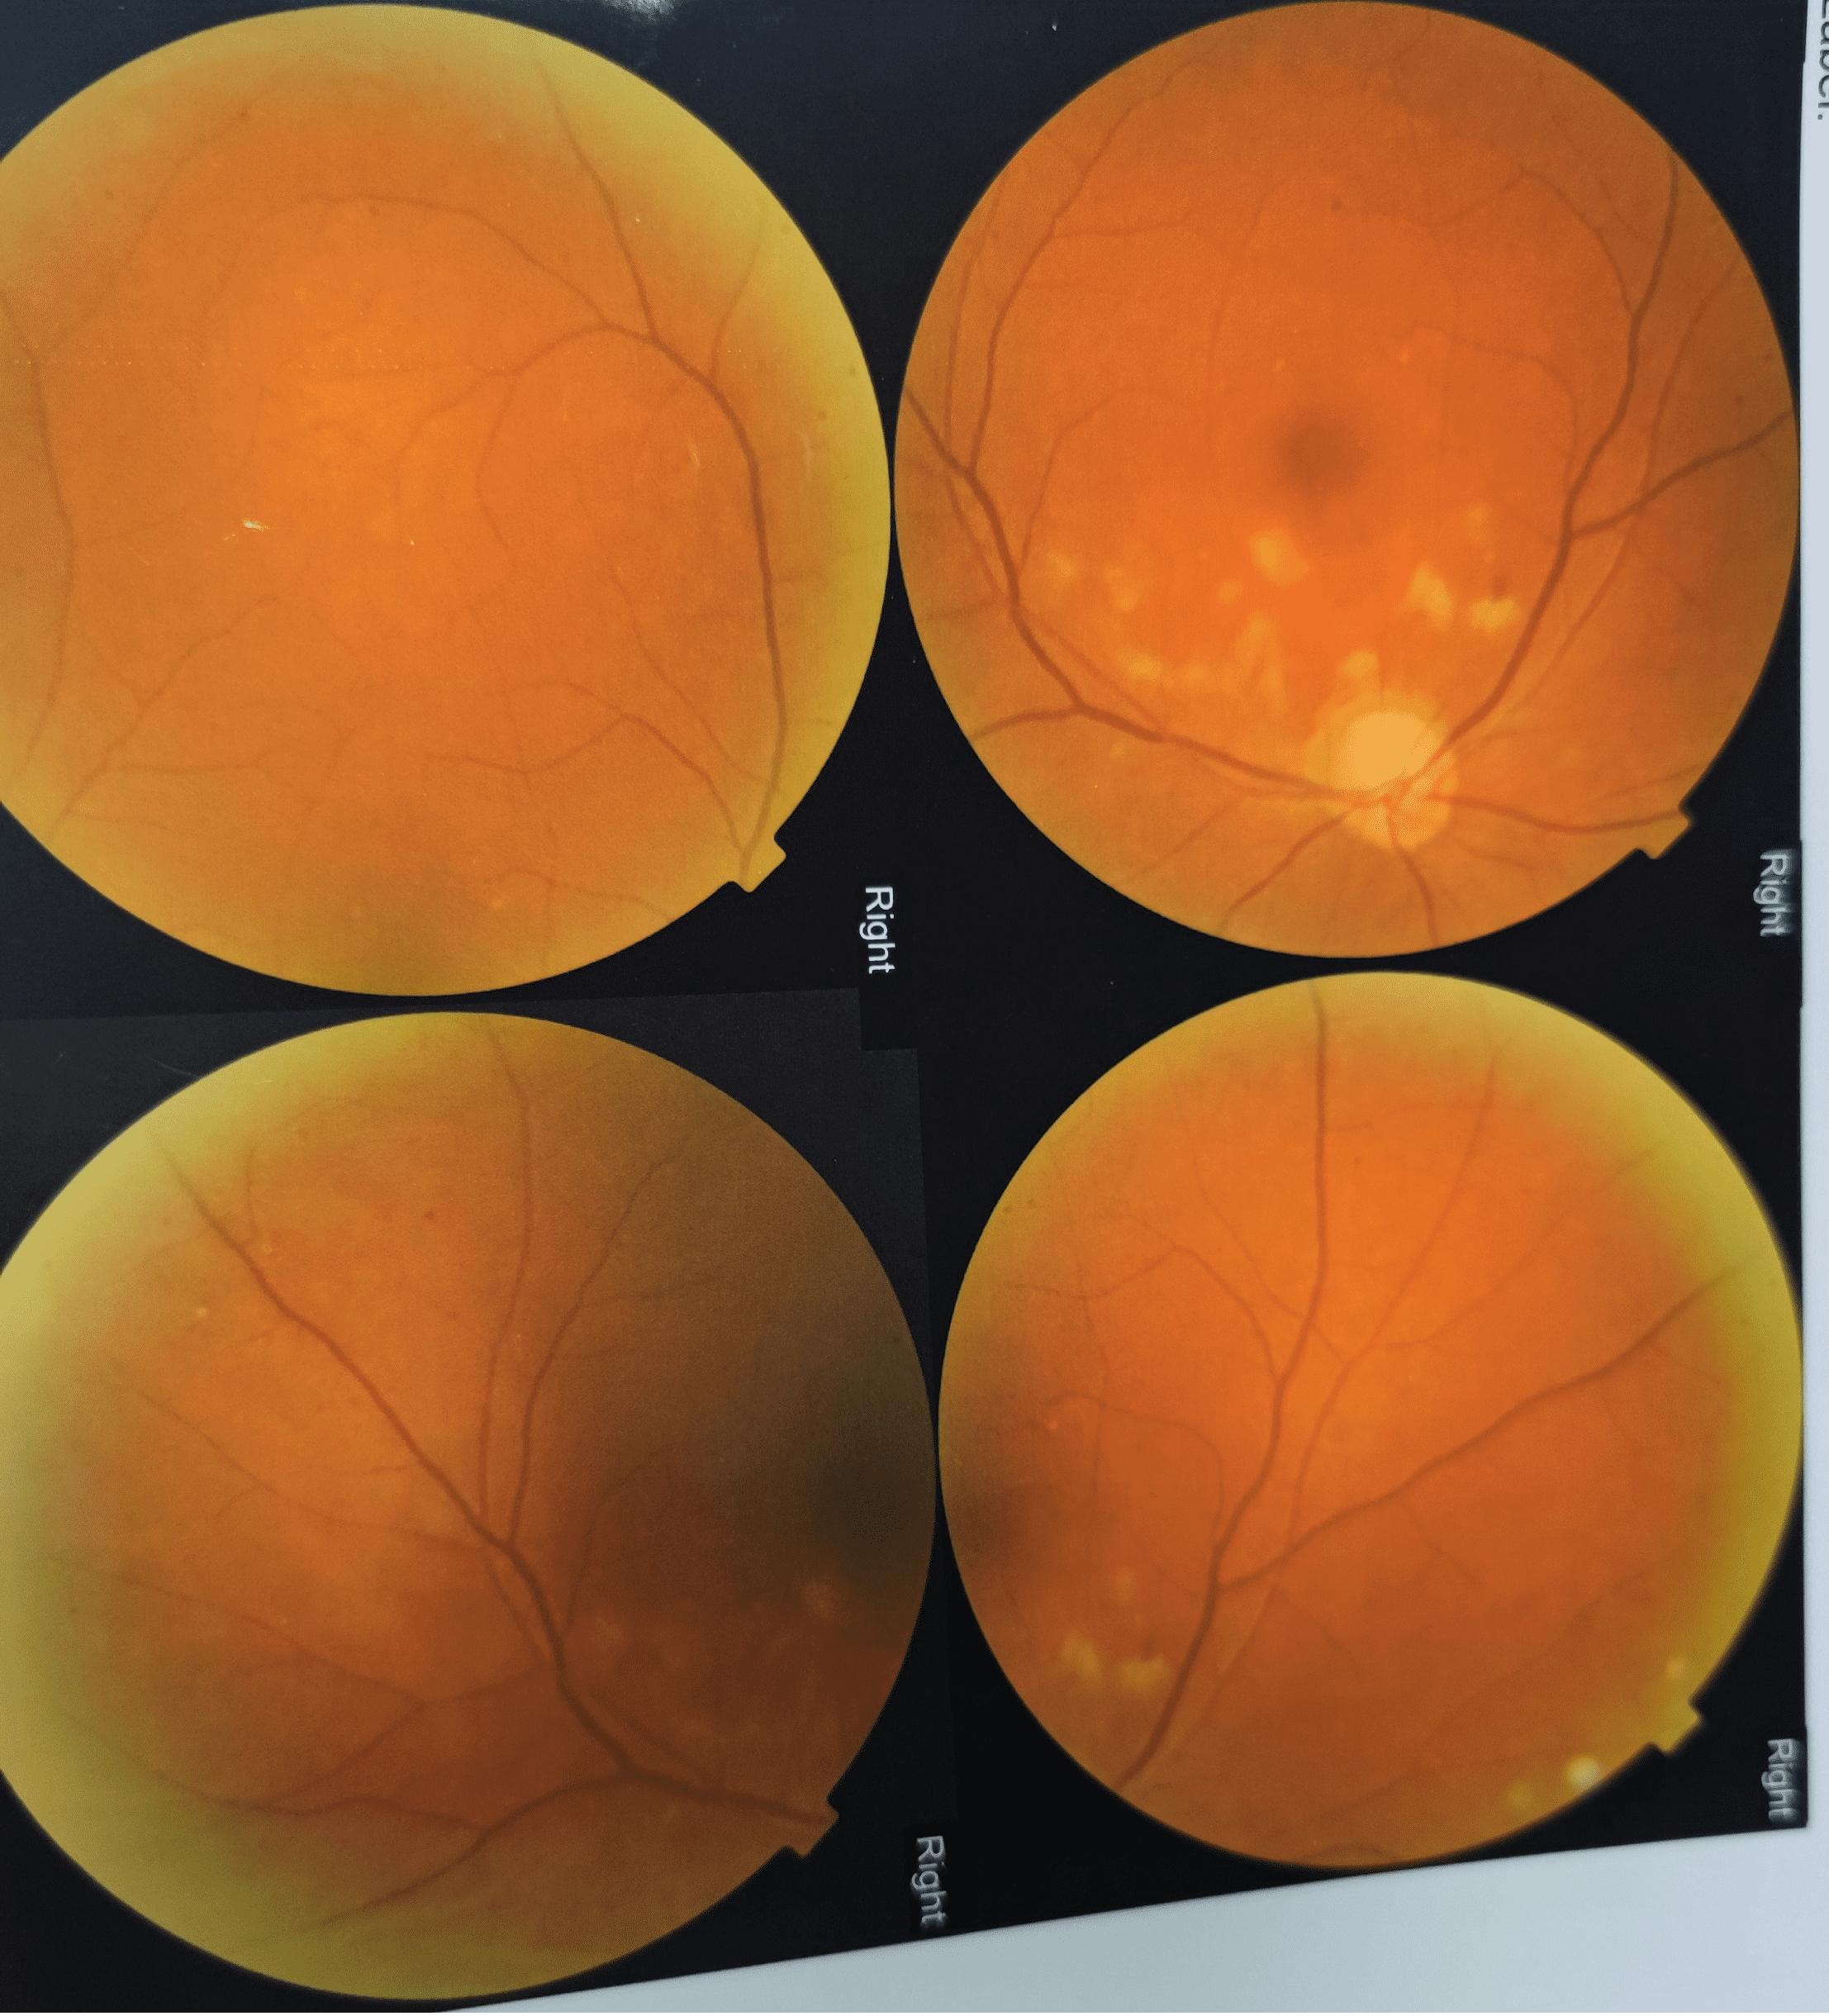

李先生找到武汉艾格眼科医院眼底病科张祺主任,张主任为他做了眼底照相、oct等眼底检查,通过检查结果,结合症状,确诊他患上远达性视网膜病变。

李先生未治疗前眼底检查影像资料

幸好李先生就医及时,经过半个月的对症药物治疗,李先生的视力从0.02提高到0.7,张祺主任判断,继续用药,三个月后,李先生有望恢复到以往1.0的正常视力。

治疗半个月后,李先生眼底检查影像图片